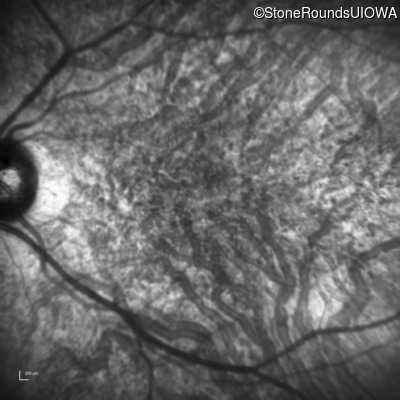

Infrared Fundus Photograph - Right - 20/40 -1

Exemplar

Infrared Fundus Photograph - Left - 10/300 sc